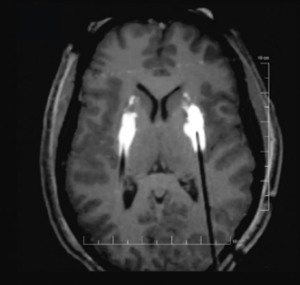

Final electrode location (right side) from the intraoperative MRI images taken during the procedure.

On June 28, 2022, functional neurosurgeon Michael C. Park, MD, PhD, performed the first deep brain stimulation (DBS) procedure in Minnesota that used the MRI-guided ClearPoint™ Neuro system. He was treating an epilepsy patient and found that the technology provided distinct advantages.

Using DBS to treat intractable epilepsy was approved by the FDA in 2018. The procedure delivers electrical stimulation to the anterior nucleus of the thalamus (ANT), a small brain structure involved in the spread of an initially localized seizure. “The ANT really can’t be mapped using electrophysiology to determine where you are when placing the electrodes,” said Park. “It’s a very small area in the brain – less than a centimeter in diameter.”

With the ClearPoint Neuro system, Park used IMRIS intraoperative MRI, another advanced technology available to neurosurgery at University of Minnesota Medical Center, which makes the process much more precise and eventually, will reduce time in the OR. He can also use the ClearPoint Neuro system to plan his approach. “You can put in a cannula or a sheath to get to the target, insert a slender probe known as a stylet, which shows up on the MRI, confirm that’s where you want to go, and then place the electrode,” said Park. “You know where you are in real-time with no guessing. That’s ClearPoint Neuro’s advantage. It’s very accurate with little room for error relative to being off target.”